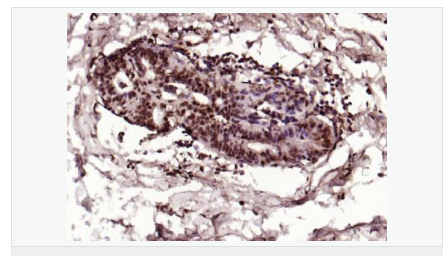

交叉反应:Human,Mouse,Rat(predicted:Dog,Pig,Rabbit,GuineaPig) 推荐应用:IHC-P,IHC-F,ICC,IF,Flow-Cyt,ELISA

| 产品应用 | ELISA=1:5000-10000 IHC-P=1:100-500 IHC-F=1:100-500 Flow-Cyt=1μg/Test ICC=1:100 IF=1:100-500 (石蜡切片需做抗原修复) not yet tested in other applications. optimal dilutions/concentrations should be determined by the end user. |